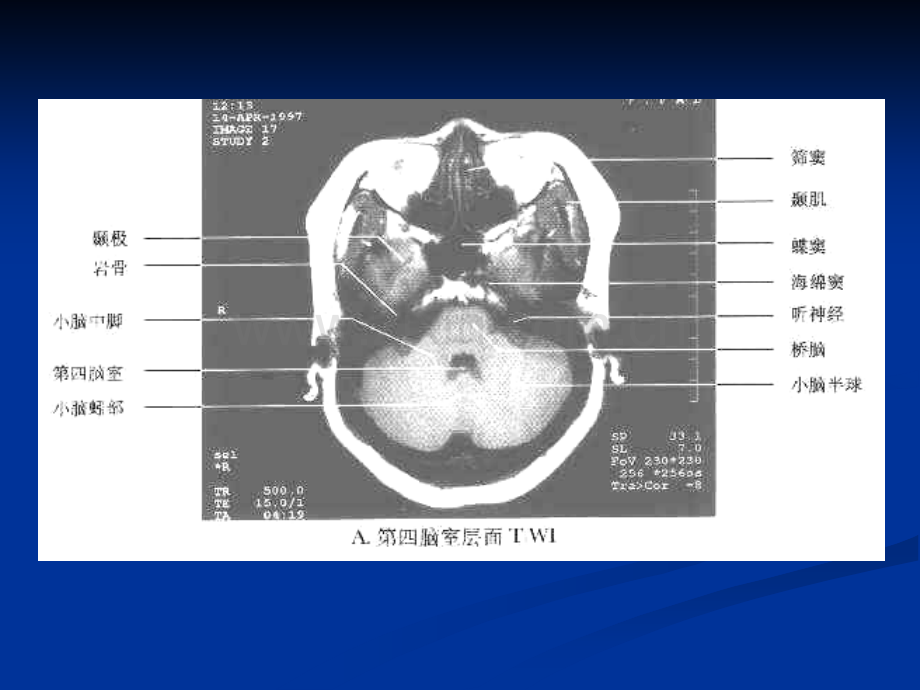

中枢神经系统常见肿瘤的MRI诊断颅内肿瘤n n是中枢神经系统常见病。是中枢神经系统常见病。n n平片诊断价值有限。平片诊断价值有限。n n血管造影可定位诊断,目前少用。血管造影可定位诊断,目前少用。n nCT,绝大多数可定位、定量诊断,绝大多数可定位、定量诊断,大多数可定性诊断。大多数可定性诊断。n nMRI,定位诊断优于,定位诊断优于CT,定性有时,定性有时有困难。有困难。颅内肿瘤n n婴儿及儿童以幕下肿瘤常见,髓母婴儿及儿童以幕下肿瘤常见,髓母细胞瘤、星形细胞瘤和室管膜瘤多细胞瘤、星形细胞瘤和室管膜瘤多见。见。n n成人则幕上多见,中年人最常见为成人则幕上多见,中年人最常见为胶质瘤和脑膜瘤,老年人为脑膜瘤胶质瘤和脑膜瘤,老年人为脑膜瘤和转移瘤。和转移瘤。n n临床表现因肿瘤类型和部位不同而临床表现因肿瘤类型和部位不同而各不相同。各不相同。神经胶质瘤(neuroglial tumors)n n又称胶质瘤(又称胶质瘤(glioma)。)。n n起源于神经胶质细胞。起源于神经胶质细胞。n n是最常见的原发性脑肿瘤,约占脑是最常见的原发性脑肿瘤,约占脑肿瘤的肿瘤的40%50%。n n包括星形细胞瘤、少突胶质细胞瘤、包括星形细胞瘤、少突胶质细胞瘤、室管膜瘤和髓母细胞瘤等。室管膜瘤和髓母细胞瘤等。星形细胞瘤(astrocytoma)n n是神经上皮源性肿瘤中最常见者。是神经上皮源性肿瘤中最常见者。n n占颅内肿瘤的占颅内肿瘤的17%17%,神经上皮源性肿,神经上皮源性肿瘤的瘤的40%40%。n n男多于女,两者比率为男多于女,两者比率为1.8911.891。(一)临床与病理(一)临床与病理n n分类:分类:传统的柯氏分类法分为传统的柯氏分类法分为级级 级分化良好,呈良性级分化良好,呈良性 级分化尚好,间变性级分化尚好,间变性 级分化差,恶性级分化差,恶性星形细胞瘤(astrocytoma)n n分化良好者:分化良好者:A.多位于大脑半球白质,少数位于多位于大脑半球白质,少数位于灰质并向白质或脑膜浸润。灰质并向白质或脑膜浸润。B.没有包膜,可沿白质纤维或胼胝没有包膜,可沿白质纤维或胼胝体纤维向临近脑叶和对侧半球发展。体纤维向临近脑叶和对侧半球发展。C.可囊变,囊内含黄色液体。可囊变,囊内含黄色液体。D.肿瘤血管近于成熟。肿瘤血管近于成熟。星形细胞瘤(astrocytoma)n n分化不良者:分化不良者:A.弥漫浸润性生长。弥漫浸润性生长。B.形态不规整,与脑实质分界不清。形态不规整,与脑实质分界不清。C.易出血、坏死,半数以上有囊变。易出血、坏死,半数以上有囊变。D.肿瘤血管形成不良。肿瘤血管形成不良。E.血脑屏障不完整。血脑屏障不完整。星形细胞瘤(astrocytoma)n n发生于小脑者:发生于小脑者:A.多位于小脑半球,亦可位于蚓部。多位于小脑半球,亦可位于蚓部。B.多为囊实性。多为囊实性。n n临床表现:临床表现:A.局灶性或全身性癫痫发作。局灶性或全身性癫痫发作。B.神经功能障碍和颅内压增高。神经功能障碍和颅内压增高。星形细胞瘤(astrocytoma)星形细胞瘤(astrocytoma)n nMRI:1.幕上星形细胞瘤:幕上星形细胞瘤:A.长长T1、长、长T2信号,以信号,以T2延长明显;延长明显;B.囊液内蛋白含量较高,囊液内蛋白含量较高,T1WI上上信号高于脑脊液,低于脑实质;信号高于脑脊液,低于脑实质;C.信号可均匀,也可不均匀;信号可均匀,也可不均匀;星形细胞瘤(astrocytoma)n nMRI:1.幕上星形细胞瘤:幕上星形细胞瘤:D.偏良性者多无强化,偏恶性者多有偏良性者多无强化,偏恶性者多有强化;强化;E.瘤周水肿,长瘤周水肿,长T1、长、长T2信号;信号;F.MRI表现在一定程度上提示恶性度。表现在一定程度上提示恶性度。级星形细胞瘤级星形细胞瘤T1WIT2WI增强增强同前病例同前病例T1WI增强增强增强增强级星形细胞瘤级星形细胞瘤T1WIT2WI增强增强同前病例同前病例冠状位增强冠状位增强 矢状位增强矢状位增强级星形细胞瘤级星形细胞瘤T1WIT2WIT1WI级级星星形形细细胞胞瘤瘤T1WI增强增强同前病例同前病例T1WI增强增强增强增强级星形细胞瘤级星形细胞瘤T1WIT2WI增强增强同前病例同前病例T1WI增强增强增强增强级星形细胞瘤级星形细胞瘤T1WIT2WI增强增强同前病例同前病例冠状位增强冠状位增强 矢状位增强矢状位增强级星形细胞瘤级星形细胞瘤T1WIT2WI增强增强同前病例同前病例冠状位增强冠状位增强 矢状位增强矢状位增强级级星星形形细细胞胞瘤瘤同前病例同前病例星形细胞瘤(astrocytoma)n n2.幕下星形细胞瘤幕下星形细胞瘤 A.与幕上星形细胞瘤相比,囊变率与幕上星形细胞瘤相比,囊变率高而水肿较轻;高而水肿较轻;B.囊性和实性部分均为长囊性和实性部分均为长T1、长、长T2信号,实性部分强化;信号,实性部分强化;C.没有骨伪影的干扰,没有骨伪影的干扰,MRI优于优于CT,可清楚分辨肿瘤与脑干的关系。,可清楚分辨肿瘤与脑干的关系。T1WIT2WI增强增强毛细胞型星形细胞瘤毛细胞型星形细胞瘤同前病例同前病例T1WI增强增强增强增强毛毛细细胞胞型型星星形形细细胞胞瘤瘤T1WIT2WI增强增强脑干星形细胞瘤脑干星形细胞瘤同前病例同前病例T1WI增强增强增强增强T1WIT2WI增强增强脑干星形细胞瘤脑干星形细胞瘤同前病例同前病例T1WI增强增强增强增强